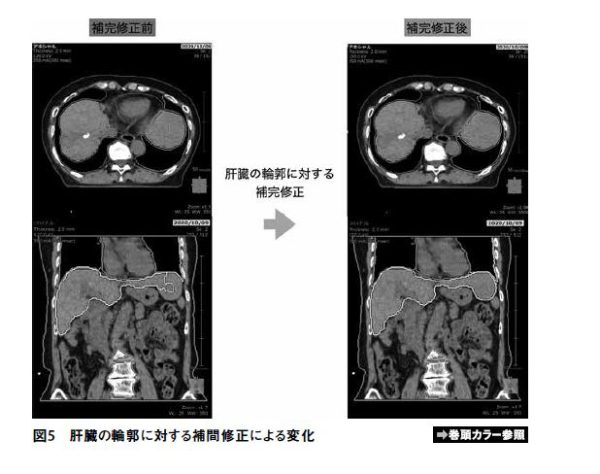

自動輪郭作成には問題点もあり、自動輪郭作成によって生成された臓器輪郭は修正をすることが簡単ではないことが多い。一から手動で輪郭描出を行う際はほとんどの治療計画装置で輪郭の interpolate(補間)ができるため、数スライスおきに輪郭描出を行い補間することで、全スライスでの輪郭作成をすることが可能である。しかし自動輪郭作成で描出された臓器輪郭はすでにすべてのスライス上で輪郭描出がされてしまっているため、修正の際に補間が使用できないことがほとんどである。そのため実際のリスク臓器と作成輪郭にずれが見られた場合、自動作成した輪郭を削除して一から手動で描出する方が早いことも少なくない。SYNAPSE Radiotherapyでは自動で作成した臓器輪郭にも補間を行うことが可能であり、個人的には非常に便利な点であると思っている。「補間用輪郭の設定」を選択した状態でいくつかのスライスにおいて輪郭を修正することで自動作成された輪郭に対しても、修正を加えたスライス間の輪郭を補間することができる。図4、5に自動作成した肝臓の輪郭に対する補間修正の方法及びその変化の一例を示す。